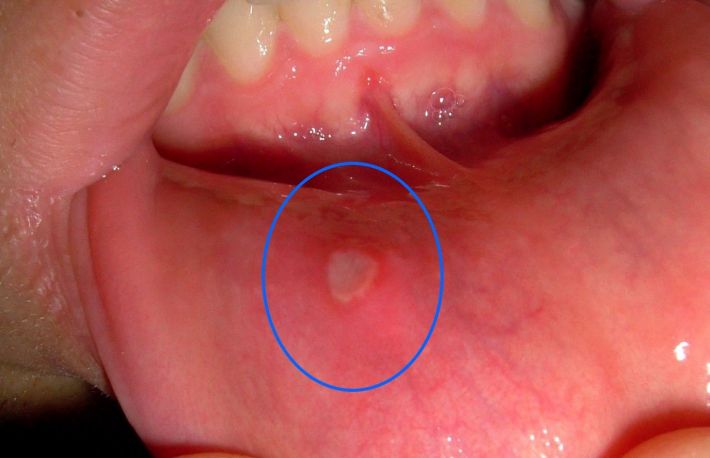

Unele forme de cancer pot fi tratate  daca  sunt diagnosticate din timp; o astfel de forma este cea de cancer la gat (faringian). Daca cancerul este depistat in faza incipienta exista sanse foarte mari de recuperare. Este foarte important sa cunosti simptomele specifice cancerului faringian pentru a putea consulta un medic specialist in acest sens.

Celulele cancerigene apar de obicei la nivelul corzilor vocale iar mai apoi invadeaza zonele vecine: laringe, amigdale, limba.